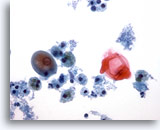

Neck FNA, malignant melanoma.

In this photo there are many single cells, and clusters of cells that contain pigment. In the center is a single plasmacytoid malignant cell, as well as naked nuclei. 20x

Neck FNA, malignant melanoma.

In this photo there are many single cells, and clusters of cells that contain pigment. In the center is a single plasmacytoid malignant cell, as well as naked nuclei.

20x